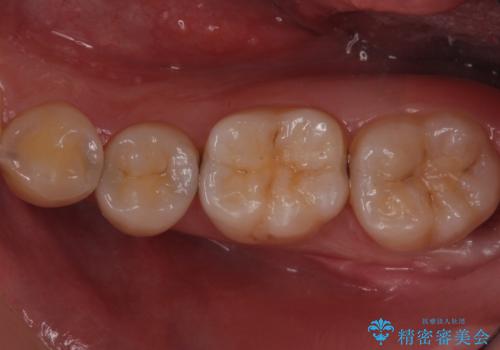

歯と歯の間の虫歯 セラミックインレーでの治療

- 矯正前の虫歯治療です。

歯と歯の間に虫歯があったため適合の良いセラミックインレーで修復処置をしていきました。